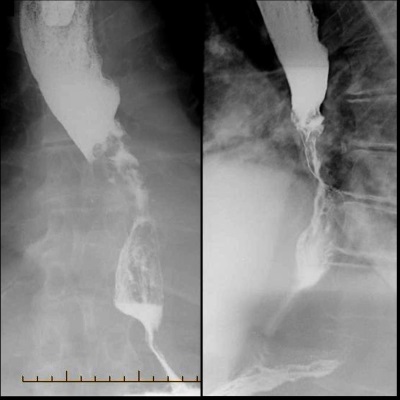

Oesophageal cancer

Until recent times oesophageal cancer was most commonly due to a squamous cell carcinoma but the incidence of adenocarcinoma is rising rapidly. Adenocarcinoma is now the most common type of oesophageal cancer and is more likely to develop in patients with a history of gastro-oesophageal reflux disease (GORD) or Barrett's.

The majority of adenocarcinomas are located near the gastroesophageal junction whereas squamous cell tumours are most commonly found in the upper two-thirds of the oesophagus.

Features

- dysphagia: the most common presenting symptom